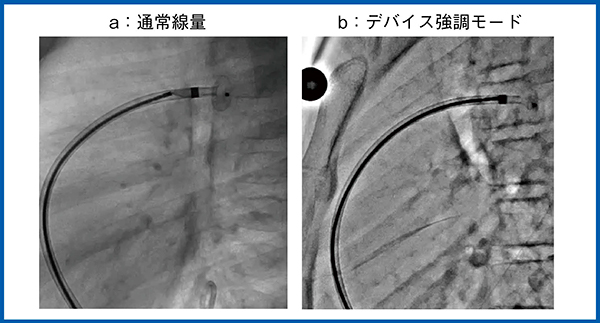

小児循環器領域においては,小児の細い血管に対して冠動脈ステントを留置する機会が増えているため,デバイスの視認性も重要となる。しかし,従来システムでは低線量の透視において,ステントなどの各種デバイスを視認しづらい場合も多かった。Alphenixシリーズでは,新しい画像処理を搭載したデバイス強調モードにてステントやガイドワイヤを明瞭に描出できるようになっている(図1)。

図1 デバイス強調モード:経皮的冠動脈形成術